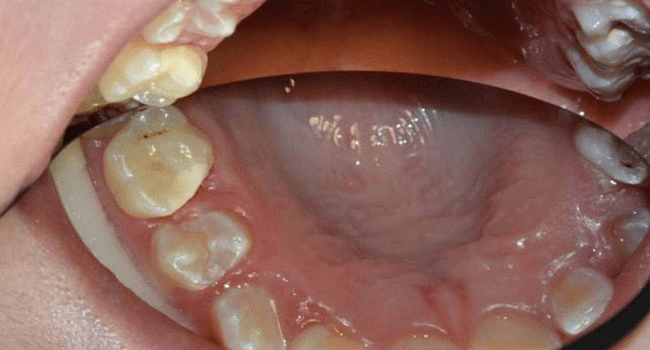

Bedre tandfyldninger med cement